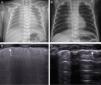

Lung ultrasound revealed an appearance compatible with RDS in all patients (Fig. 1C): compact, diffuse and symmetrically distributed B lines in both lungs with a thickened and irregular pleural line. The transtracheal placement of the ETT was verified in all cases. Lung sliding and diaphragmatic excursion were observed on the right side in all patients, but in two of them lung sliding and diaphragmatic excursion were absent in the left side coinciding with the presence of the lung pulse sign in both. This had been suspected previously during lung auscultation in one of these two patients.

(A) Chest radiograph in a newborn with respiratory distress syndrome. (B) Chest radiograph of the newborn at the time of discharge. (C) Longitudinal lung ultrasound in the same patient, showing a diffuse and compact pattern of lines. The arrow points at the thickened and irregular pleura. Once the patient was intubated, lung sliding was observed bilaterally. (D) Longitudinal lung ultrasound of the patient with a normal hyperechoic pleural line. A lines are thin and parallel to one another, with discernible rib shadows confirming normal appearance without B lines or comet tail artefacts.

The lung ultrasound performed prior to discharge showed a normal appearance (Fig. 1D).